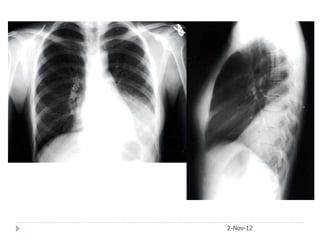

• #20 PA film showing consolidated right upper lobe. Lateral film showing consolidation limited inferiorly by horizontal fissure (arrows).